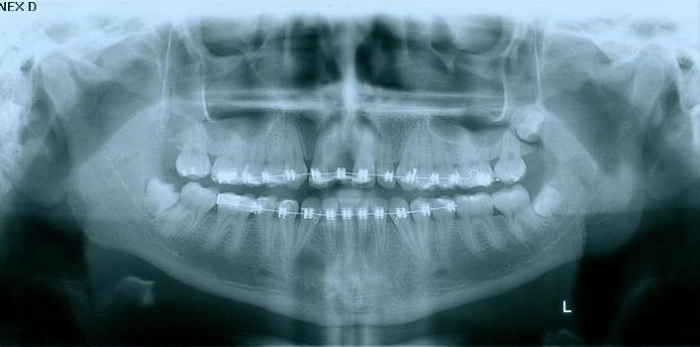

Raio x em 2014, após enxerto em bloco com osso da mandíbula.